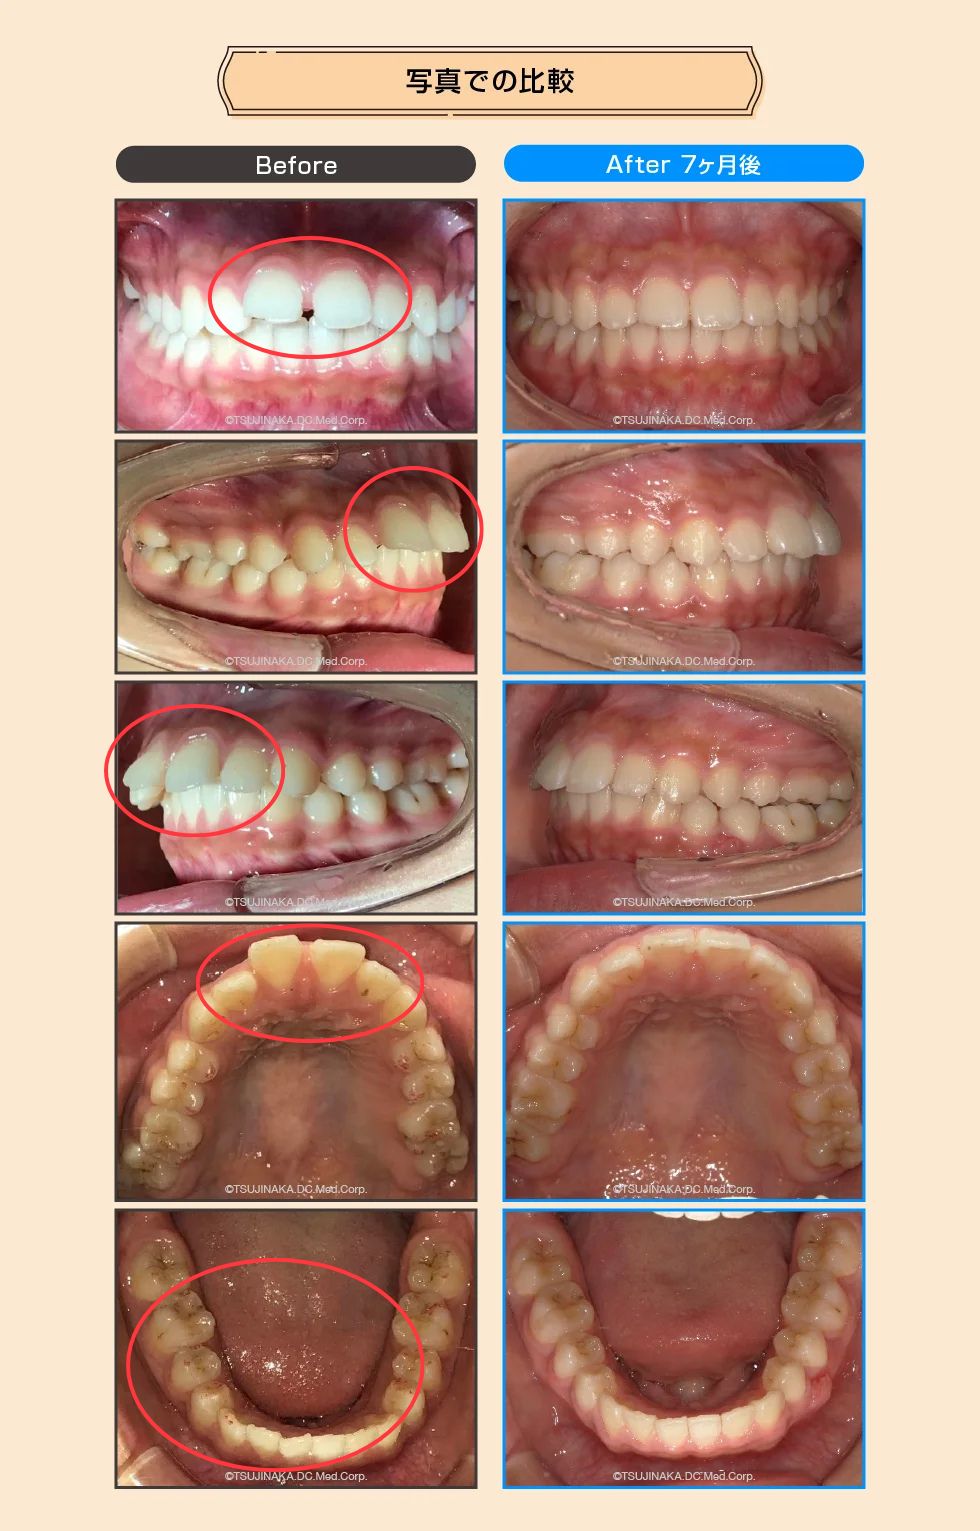

【症例No.7345】小学校の頃から歯が前に出ているのとすきっ歯が気になっていた

小学校の頃から歯が前に出ているのとすきっ歯が気になっていた

前歯のすき間や前歯が出ていることが気になるとのことでご相談いただきました。マウスピース型矯正装置を用いた矯正治療を行い、必要に応じて顎間ゴム(ゴム掛け)を併用しながら、歯列・咬合関係の改善を目指しました。

| 主訴 | 前歯のすき間(すきっ歯)と前歯が出ていることが気になる |

| 診断名 | 歯間離開(正中離開)/上顎前突/下顎叢生 |